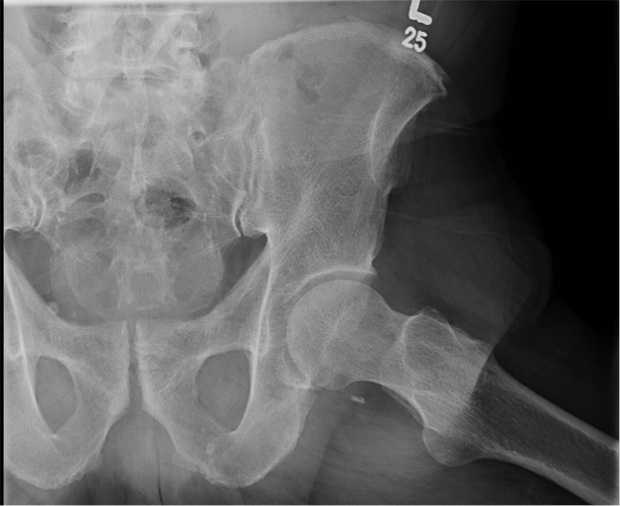

Diagnostic Testing. The evaluating clinicians obtained AP (Figure 1) and lateral (Figure 2) radiographs as well as magnetic resonance arthrogram (MRA) images of the left hip (Figures 3 and 4).

Figure 1. Anterior posterior (AP) radiograph of the pelvis is shown.